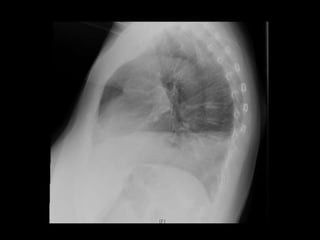

AR: Hipofonesis en base pulmonar dcha, sin otros ruidos sobreañadidos

CASO CLÍNICO EXPLORACIÓN FÍSICA AC:Rítmico, sin soplos o extratonos AR: Hipofonesis en base pulmonar dcha, sin otros ruidos sobreañadidos Abdomen: RHA +, blando, depresible, sin masas ni megalias, no doloroso Genitourinario: PPL derecha dudosa + Ap. Locomotor: Dolor a la palpación región dorso-lumbar derecha y costado derecho, que aumenta en intensidad a la inspiración profunda Extremidades: sin edemas, no signos de compromiso circulatorio, pulsos distales mantenidos